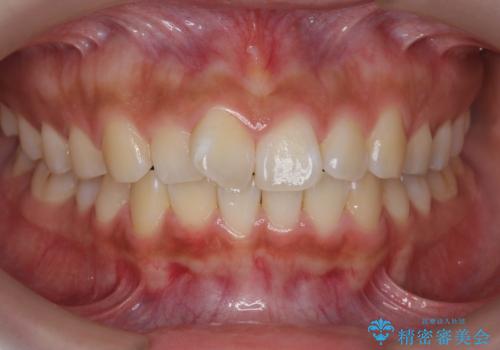

- 前歯の目立つねじれを矯正治療で治したい、と来院されました。

マウスピース矯正を始める前に、ねじれを取るのが短期間で済む部分ワイヤー小矯正を行うことで、全体的な治療期間を短くする治療計画を実行していきます。

前歯のねじれはマウスピース矯正の苦手な動きになり、治療期間が長くなる原因になりやすいです。